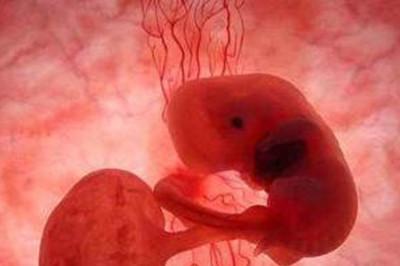

受精是精子穿入卵子形成受精卵的过程。受精一般发生在排卵后的12小时之内的输卵管壶腹部,整个受精过程大约需要24小时。

在千山万水人海相遇,原来你也在这里。发育正常并已获能的精子与发育正常的卵细胞在限定时间内相遇是受精的前提条件。